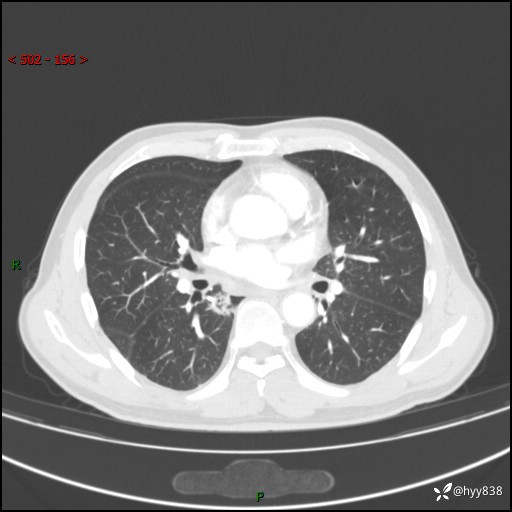

69岁/男,发现肺部病变6天。该有的征象都有,肉芽肿 VS 肿瘤,一念之间---(有结果)

主诉:发现肺部病变6天。

现病史:患者6天前于我院泌尿外科住院,住院期间行胸部CT检查,提示“肺部病变”,患者无畏寒、发热、盗汗、咳嗽、咳痰、咯血、胸痛、呼吸困难,无反酸、腹痛、腹泻、头痛、头晕等不适。未予特殊处理,现为进一步诊治,门诊以“肺肿物”收入我科。 患者本次起病以来,精神食欲尚可,大小便正常,体力及体重无明显变化。

胸部CT平扫+增强